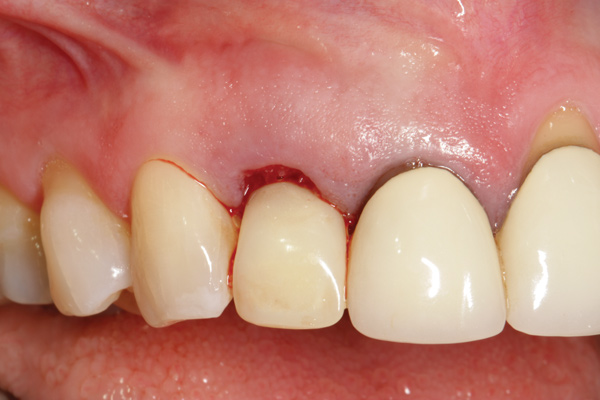

When placing multiple implants in the esthetic zone, Tarnow et al reported a lower height of the bone crest in areas with an inter-implant distance of ≤ 3 mm compared with areas with > 3 mm between the implants and suggested that this difference may be the result of lateral bone loss at the implants.53 Finally, management of subgingival abutment contour and definitive crown restoration shape that is harmonious with the surrounding periodontium is needed to maintain long-term soft-tissue health and stability (Figure 11 and Figure 12).